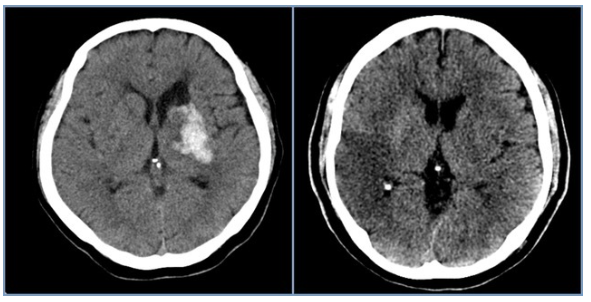

4. 혈전 용해 치료의 골든타임

뇌경색의 치료는 막힌 혈관을 뚫는 혈전 용해술이 핵심이며, 증상 발현 후 4.5시간 이내에 치료해야 효과적입니다. 따라서 증상 발현 시간을 정확히 기억하고 지체 없이 119에 신고하여 병원으로 이송되어야 합니다.